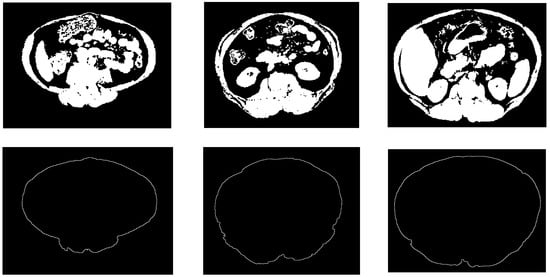

Figure 7. Samples from the abdomen wall boundary detection results. The top row is the non-fat binary images, the bottom row is the abdomen wall boundary images.